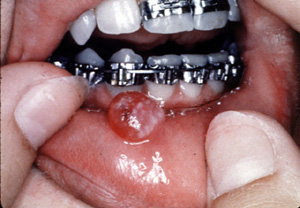

Aquí hay un

ejemplo típico degranuloma

piógeno vascular, focalmente ulcerado. Éstos son generalmente

asociados con algún tipo de irritación local; en este caso es

probablemente el aparato ortodóntico. Por el color usted puede ver que

la lesión es notablemente vascular y está casi exclusivamente

compuesto de tejido de granulación.